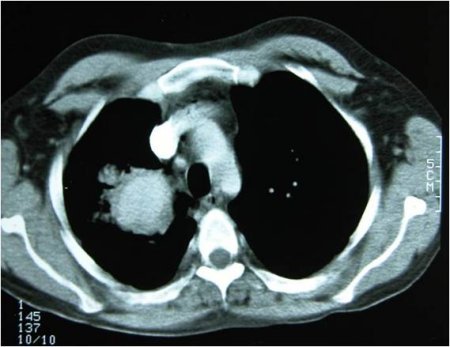

Síndrome de Behçet

Aneurisma pulmonar

Do acervo de Yusuf Yazici, MD

Veja esta imagem em contexto nas seguintes seções: